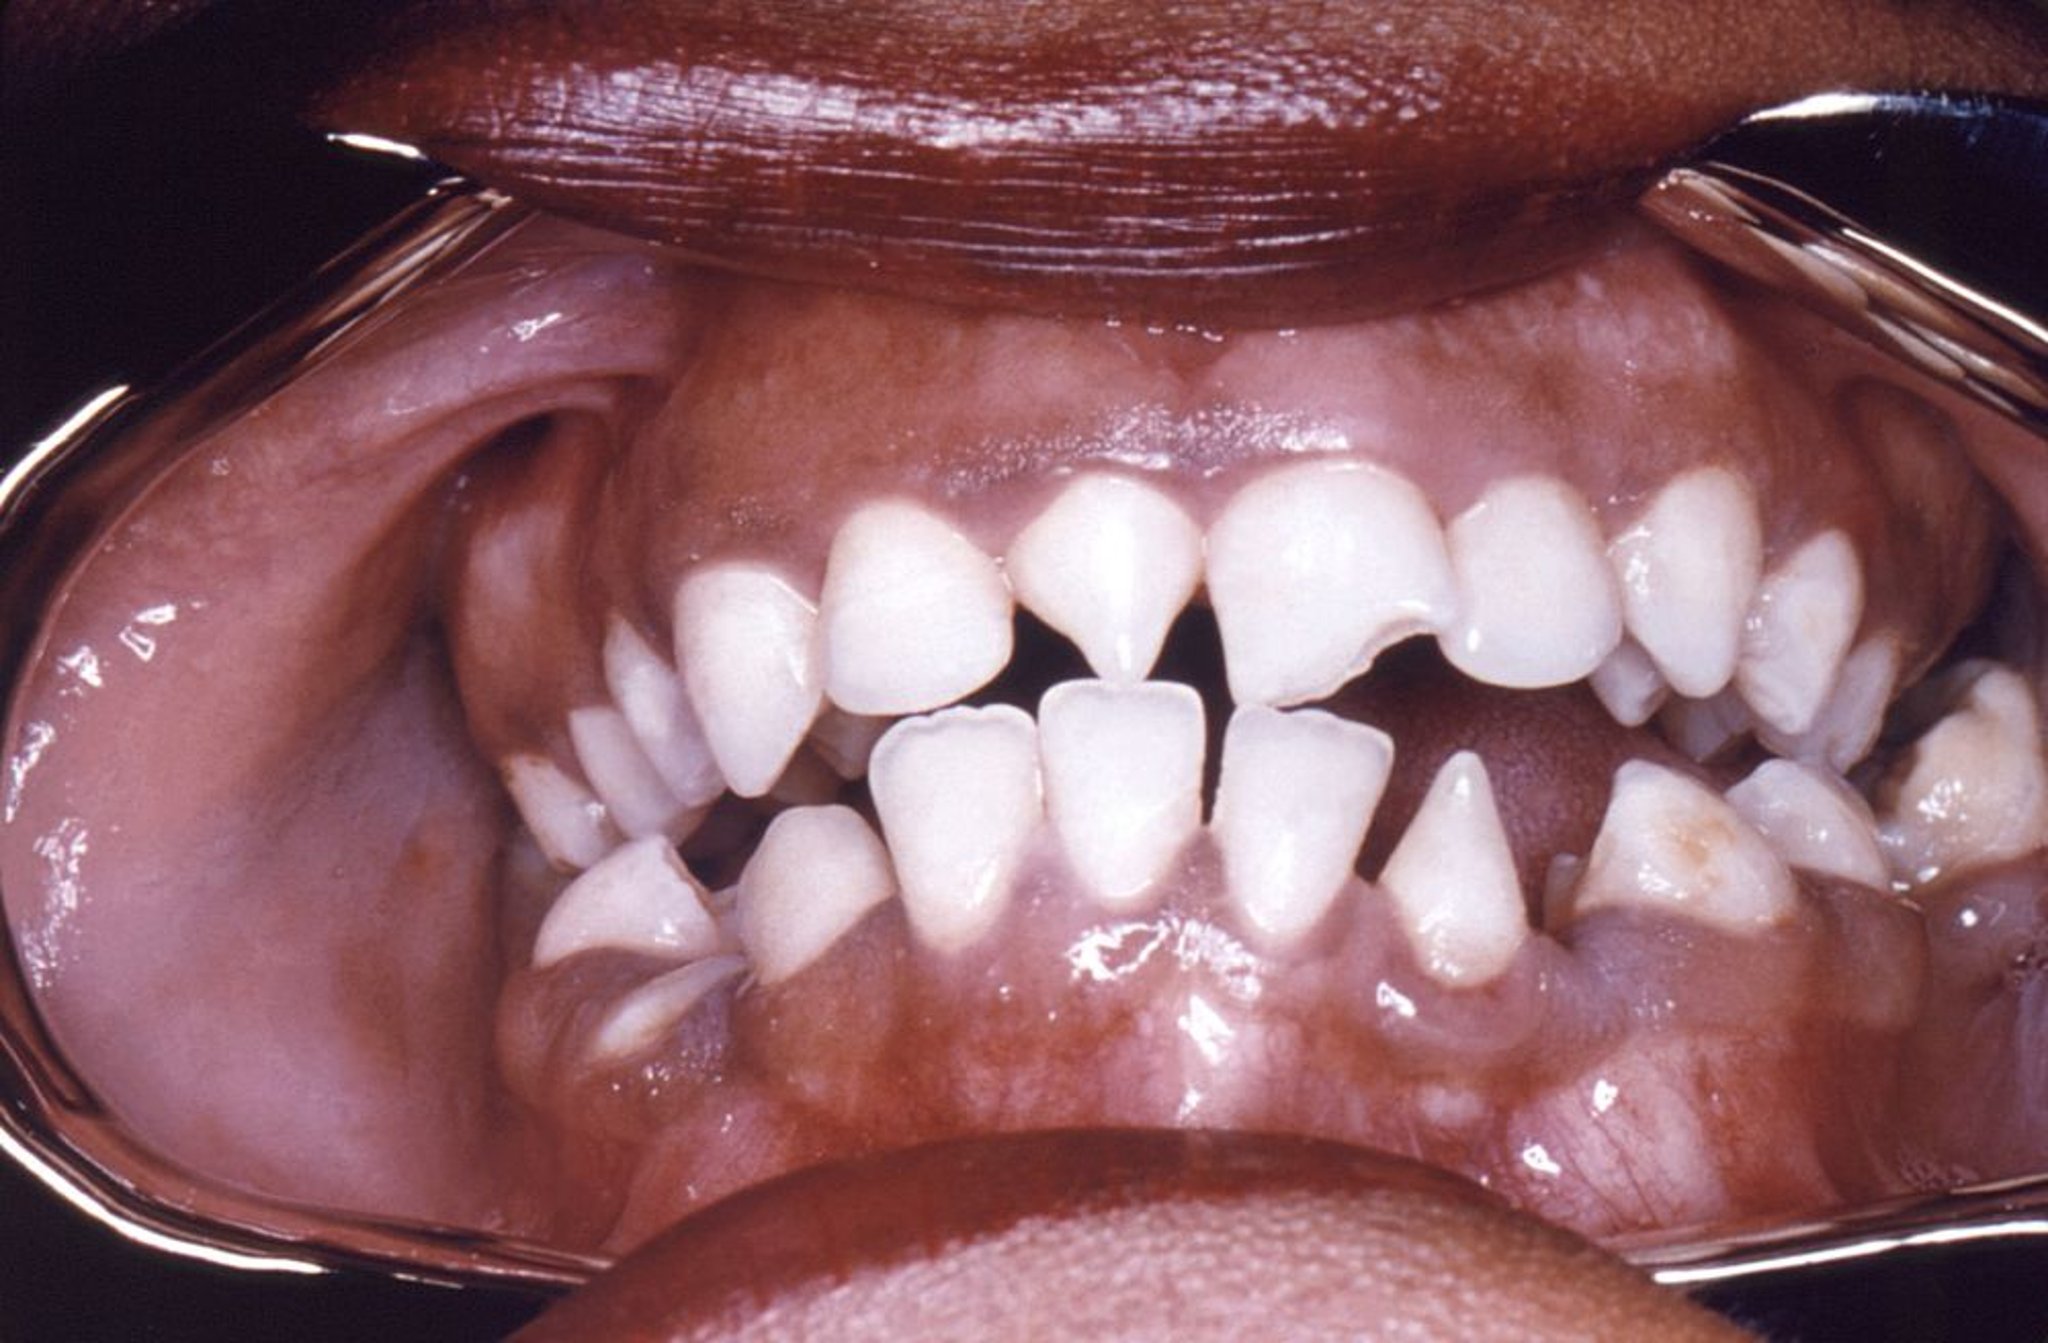

Incisivos de Hutchinson

Esta foto mostra deformidade em forma triangular dos incisivos superior direito e inferior esquerdo causada pela sífilis congênita.